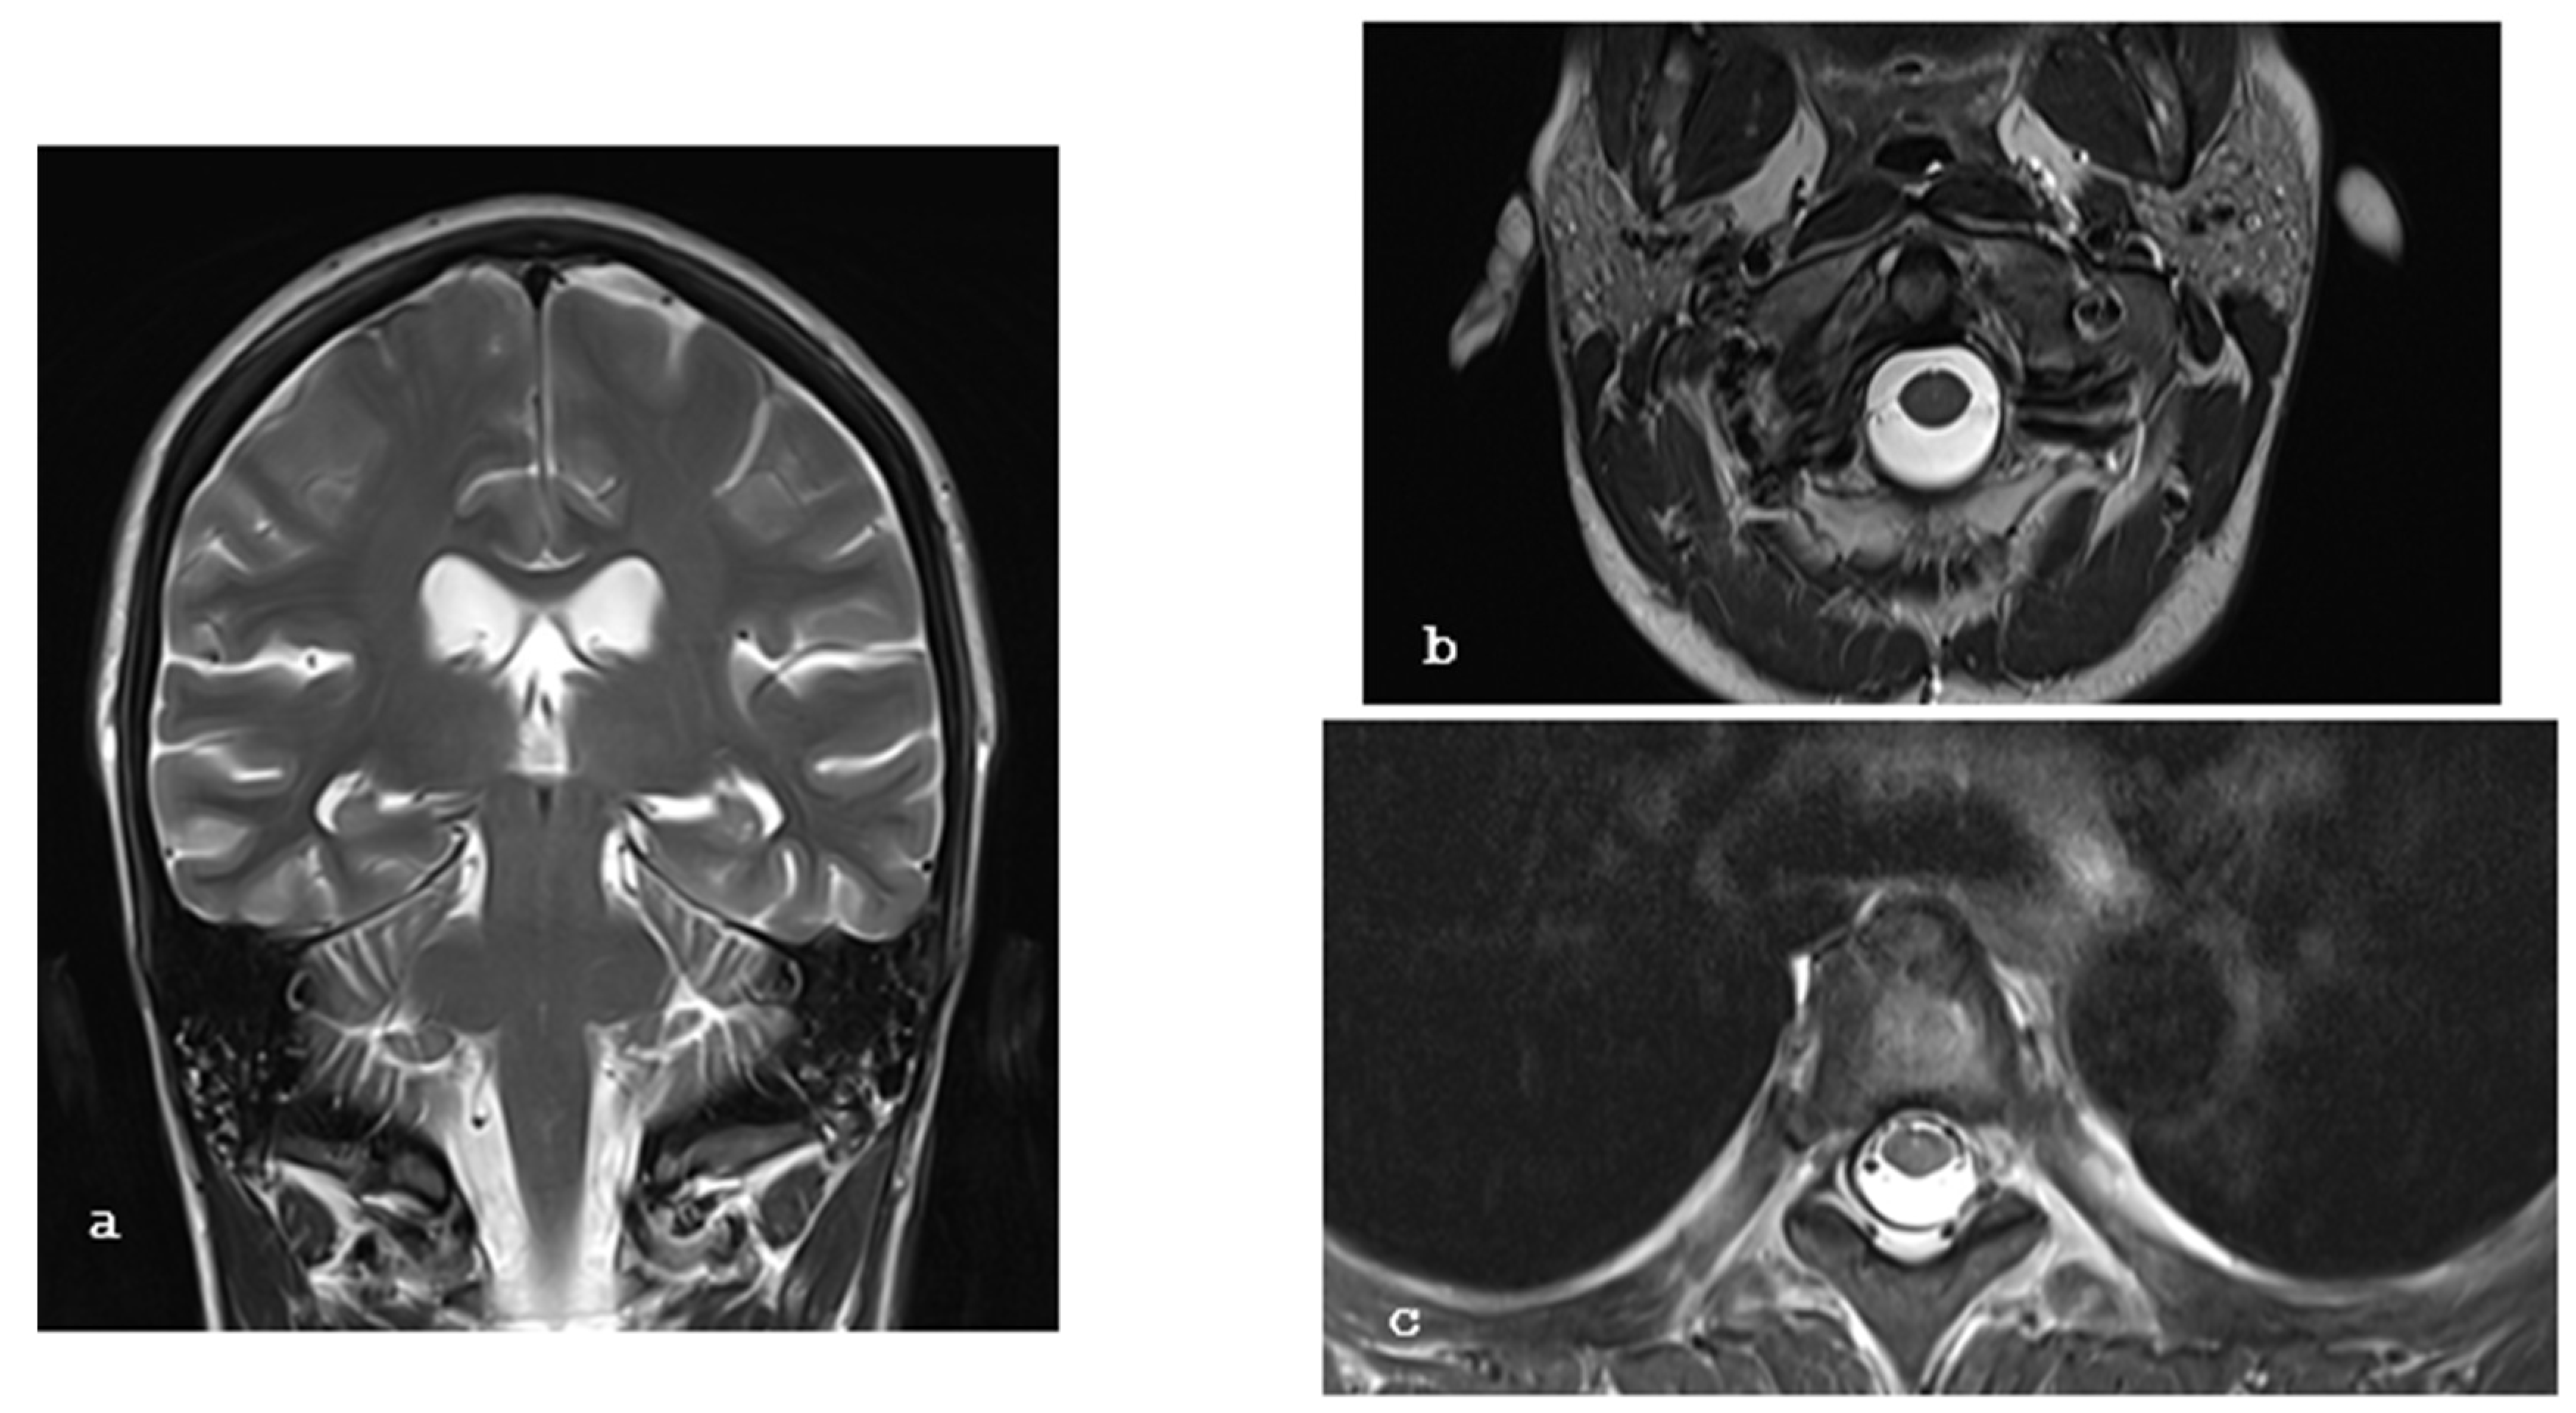

2. Case Report